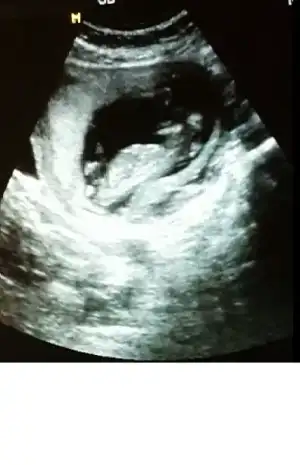

kızlar cinsiyet tahmini yapabilen var mı :)

• tp10.webp

tp10.webp

11,6 KB · Görüntüleme: 119

• tp7.webp

tp7.webp

10,6 KB · Görüntüleme: 122